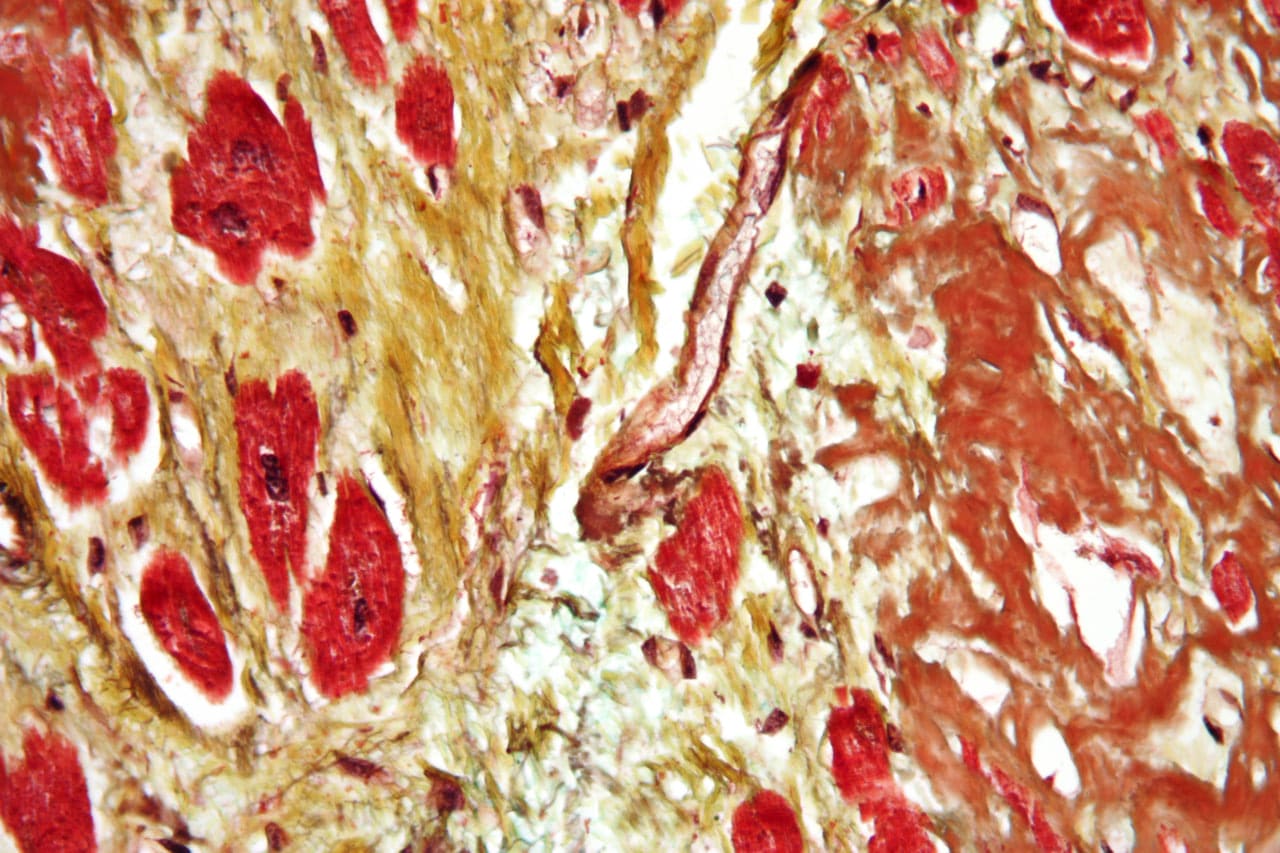

У пациентов с сердечной недостаточностью препарат продемонстрировал 28% сокращение риска инфарктов, инсультов и кардиологической смертности. Независимость результатов от возраста, пола и индекса массы тела подтверждает широкие возможности применения. Пациенты с ожирением теряли до 10% лишнего веса, что стало дополнительным позитивным эффектом.

Сергей Шалаев, заведующий кафедрой кардиологии и автор исследования, подчеркивает: «Семаглутид безопасен даже для пациентов без диабета, сокращая сердечно-сосудистые осложнения на 20%». Научная команда под руководством Людмилы Суплотовой и при участии Евгения Межонова, Алевтины Серещевой и Евгения Петрика добилась включения препарата в европейские клинические стандарты для пациентов с высоким кардиориском.